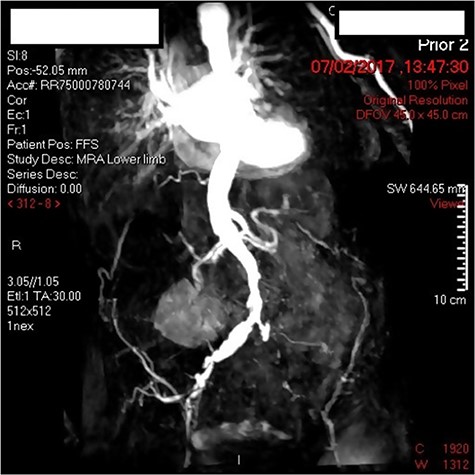

A 90-year-old female with bilateral leg ulcers and rest pain had presented at the department for bilateral iliac angioplasty and stenting. The multidisciplinary team deemed her as not fit for an open procedure due to multiple comorbidities including, type 2 DM, chronic kidney disease, hypertension, hypothyroidism and glaucoma. The lesion was also a TransAtlantic Inter-Society Consensus (TASC) Type B lesion, which would be more suitable for an endovascular procedure. Preoperatively the patient had an arterial duplex of the aortoiliac segment and a magnetic resonance angiogram (MRA) demonstrating 70% stenosis of the offending vessel (Fig. 1).